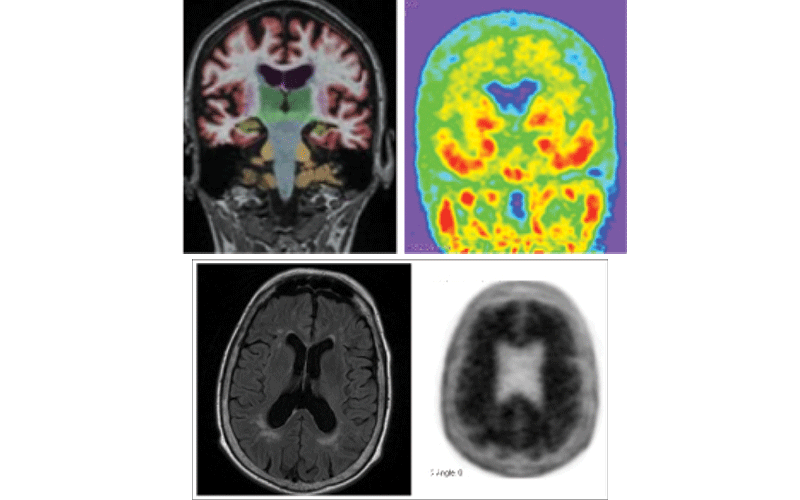

Fig Top. PET-MRI coronal brain T1 with quantitative structural segmentation for hippocampal volumes (left). Positive tau PET with 18F-flortaucipir (right).

Fig Bottom. PET-MRI axial brain FLAIR demonstrating mild white matter ischemic disease but no infarct (left). Positive amyloid PET with 18F-florbetapir (right).

Research images courtesy of Tammie L.S. Benzinger, MD, PhD